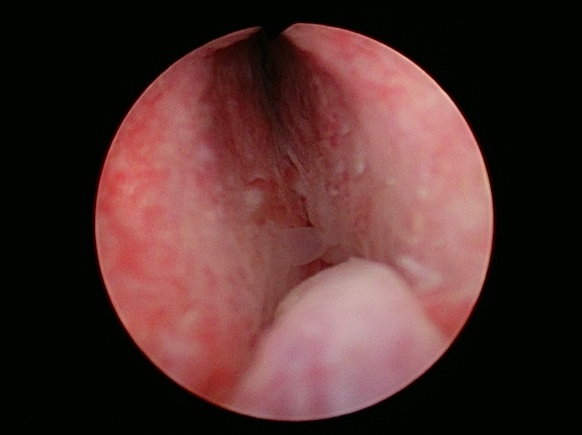

前立腺切除前

前立腺切除後